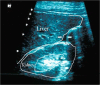

Background: Diagnosis of blunt abdominal trauma is a real challenge even for experienced trauma surgeons. Diagnostic tools that help the treating doctor in optimum management of blunt abdominal trauma include; Focussed Assessment Sonography for Trauma (FAST), Diagnostic peritoneal lavage (DPL) and CT scan.

Findings and conclusions: FAST is useful as the initial diagnostic tool for abdominal trauma to detect intraabdominal fluid. With proper training and understanding the limitations of ultrasound, the results of FAST can be optimized. DPL is indicated to diagnose suspected internal abdominal injury when ultrasound machine is not available, there is no trained person to perform FAST, or the results of FAST are equivocal or difficult to interpret in a haemodynamically unstable patient. In contrast, in haemodynamically stable patients the diagnostic modality of choice is CT with intravenous contrast. It is useful to detect free air and intraperitoneal fluid, delineate the extent of solid organ injury, detect retroperitoneal injuries, and help in the decision for conservative treatment. Helical CT is done rapidly which reduces the time the patient stays in the CT scan room. Furthermore, this improves sagittal and coronal reconstruction images which are useful for detecting ruptured diaphragm.